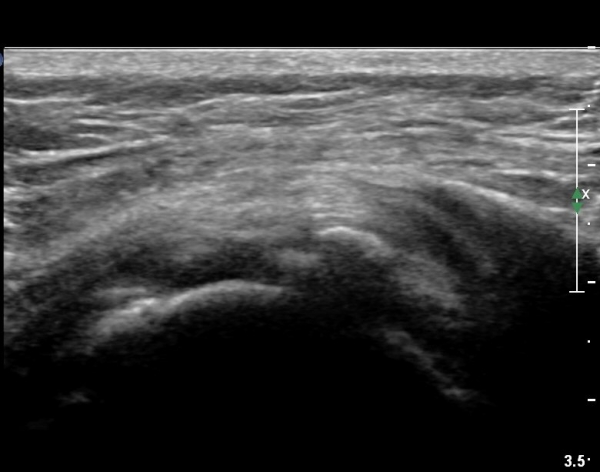

ÃÊÀ½ÆÄ °Ë»ç

Ä¡·á

Á¡¾×³¶³» ÁÖ»çÄ¡·á¿Í ¼®È¸ÀÇ ÁÖ»ç¹Ù´Ã ÀÚ±Ø(needling)